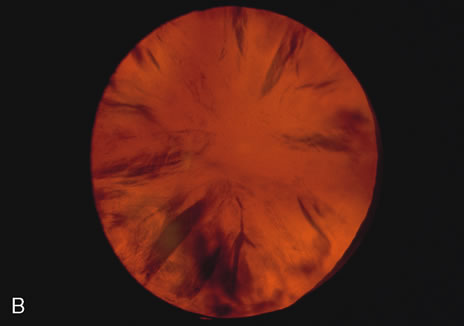

are the shells of the nucleus and cortex that are concentric

to each other (Figs. 2, 5, 6, and 7).   Fig. 2. Brunescent (brown) nuclear cataract using (A) narrow beam slit illumination and (B) retroillumination. The cataract is best seen by direct slit illumination. In

retroillumination, as seen in this image, the outline of

the nuclear cataract may be seen due to its increased refractive index, although

the cataract does not cast any shadows. Because of its central

location, this cataract may cause distortion of images early in their

development. Fig. 2. Brunescent (brown) nuclear cataract using (A) narrow beam slit illumination and (B) retroillumination. The cataract is best seen by direct slit illumination. In

retroillumination, as seen in this image, the outline of

the nuclear cataract may be seen due to its increased refractive index, although

the cataract does not cast any shadows. Because of its central

location, this cataract may cause distortion of images early in their

development.

same patient taken over time to document and track changes. The broad beam is useful for examining cortical cataracts especially spokes

and water clefts (Fig. 2), which tend to be large and irregular. It is also useful in posterior

beams. Retroillumination uses the light reflected from the fundus to highlight

opacities. This is very useful in examining cortical and posterior subcapsular

cataracts (Figs. 1, 3, 7, and 8). However, some cortical water clefts and early posterior subcapsular

opacities may not be easily seen with retroillumination if they are

not dense enough to cast shadows or only refract the retroilluminate

light; these can be best seen with the broad beam. Using retroillumination

on nuclear cataracts does not give much information because these

usually do not cast shadows. However, as seen in Figure 2B, a change in the refractive index can be seen toward the center. Usually, the

outline of the nuclear cataract can be seen as a result of a “magnifying

lens” artifact. This is also easily observed during

direct and indirect ophthalmoscopy. Several retroillumination cameras (modified

slit lamps with the slit beam fixed for retroillumination

and depolarizers built in to remove corneal reflex from the image) have

been developed and are being used for documenting cortical

and posterior subcapsular cataracts.49, 50 |